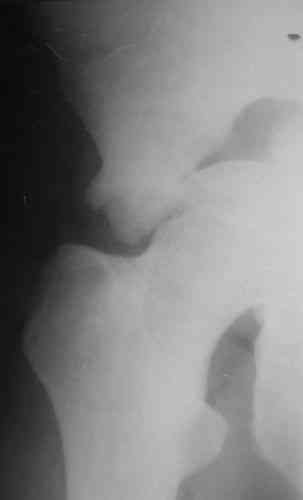

На показанных снимках повреждение правого КПС не очень заметно...

У меня создалось впечатление( одна из РГ), что участок суставной поверхности нагрузочной зоны вертлужной впадины вдавлен( постарайтесь сделать КТ). Если это подтвердиться, то из внутритазового доступа отрепонировать будет невозможно.